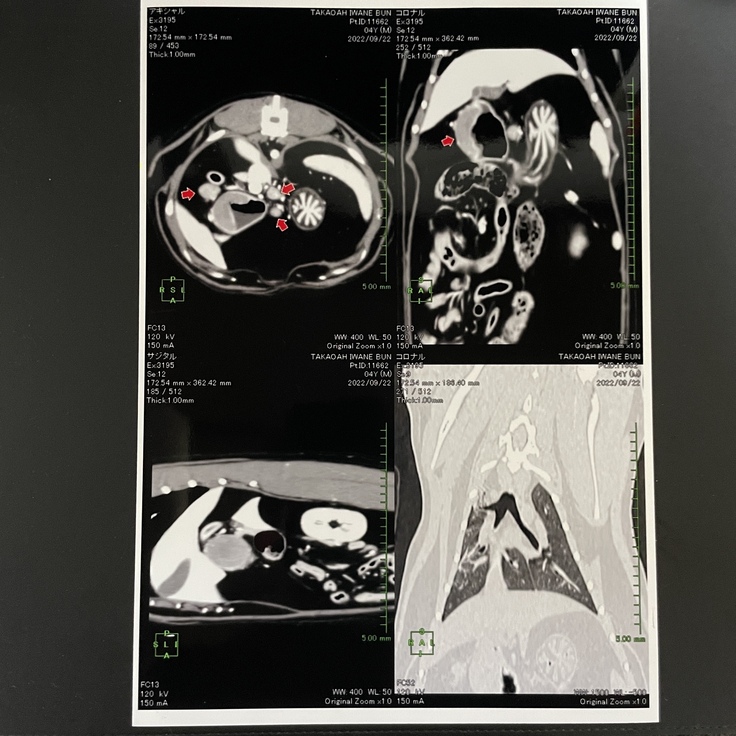

処方されたお薬では改善されず9/16に再度診察に行き、血液検査、レントゲン検査、超音波検査をして血液にSAAの異常、胃の出口付近に1cmの厚みがあり明らかに異常があることが判りました。

更に抗生物質を増やし、内服薬を数日続けましたが再度超音波検査した結果変化がなかった為、9/21内視鏡検査、CT検査、病理検査を行った結果、胃リンパ腫(消化器型)との診断を受けました。

ぶんちゃんが受けているCHOP療法という抗がん剤治療内容と直近の診断書です。

(※病院からの掲載許可を得ております。)

2022年9月22日

CT検査、内視鏡検査 胃リンパ腫と診断される。 2022年9月27日 病理検査報告書にて大細胞性消化器型悪性リンパ腫と確定診断される。